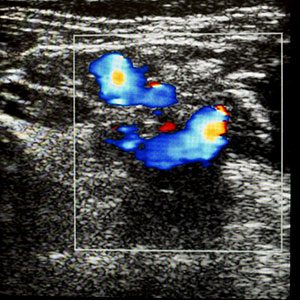

Doppler scans measure the blood flow through the umbilical cord and different parts of the fetal body like the fetal brain and liver. This scan shows whether the fetus is getting all the oxygen and nutrients that it needs via the placenta. This scan is usually combined with the growth scan.

Ultrasound Doppler scan showing blood flow in fetal umbilical cord to monitor baby’s growth and placental circulation during pregnancy